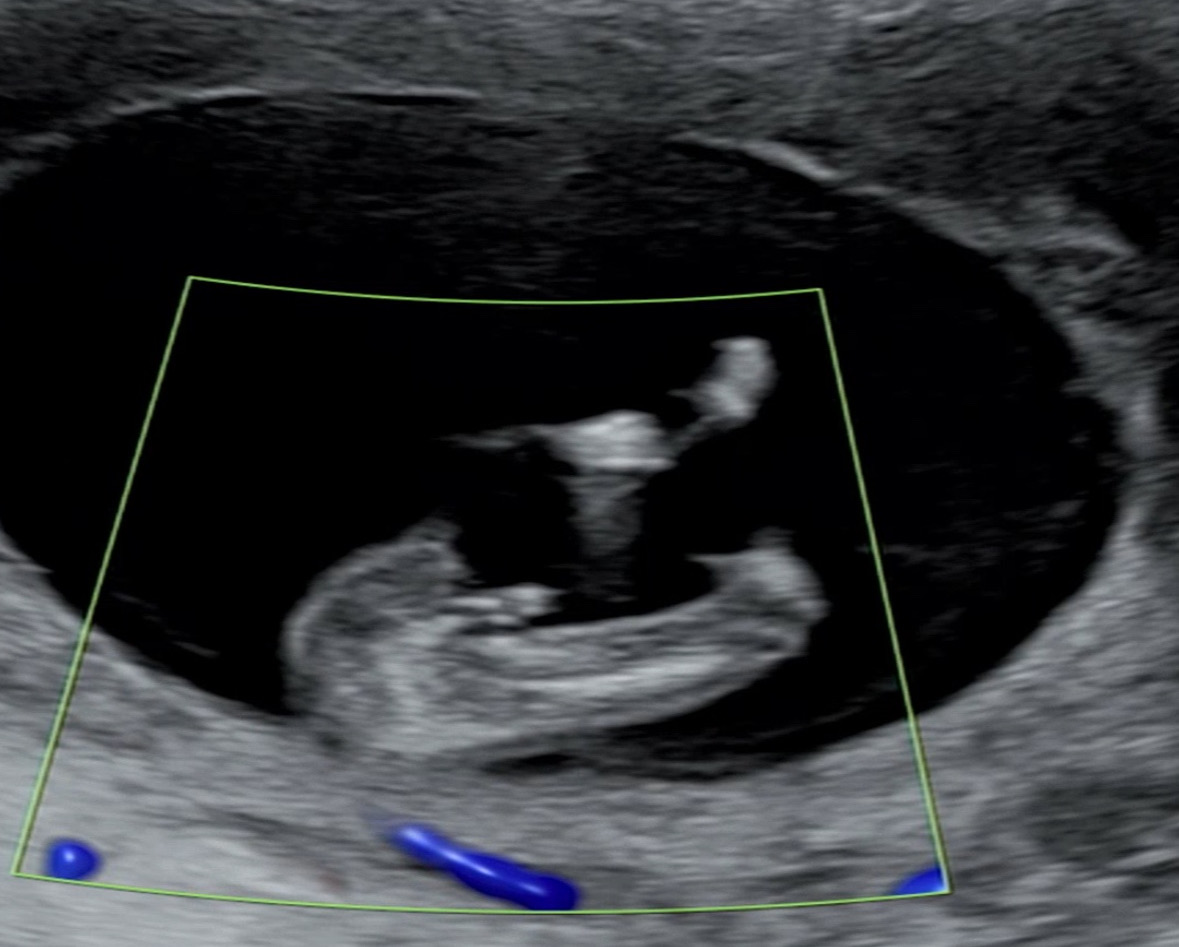

12주4일 초음파 성별반전?

아들일까요 딸일까요ㅎㅎㅎㅎ 성별반전 기대해도 될까요?ㅎㅎㅎ

12주엔 아들딸 다 튀어나왔는데 저정도면 아들같긴해여.. 저희딸도 12주에 뭐가 있었는데 저정도는 아니었어요..!!